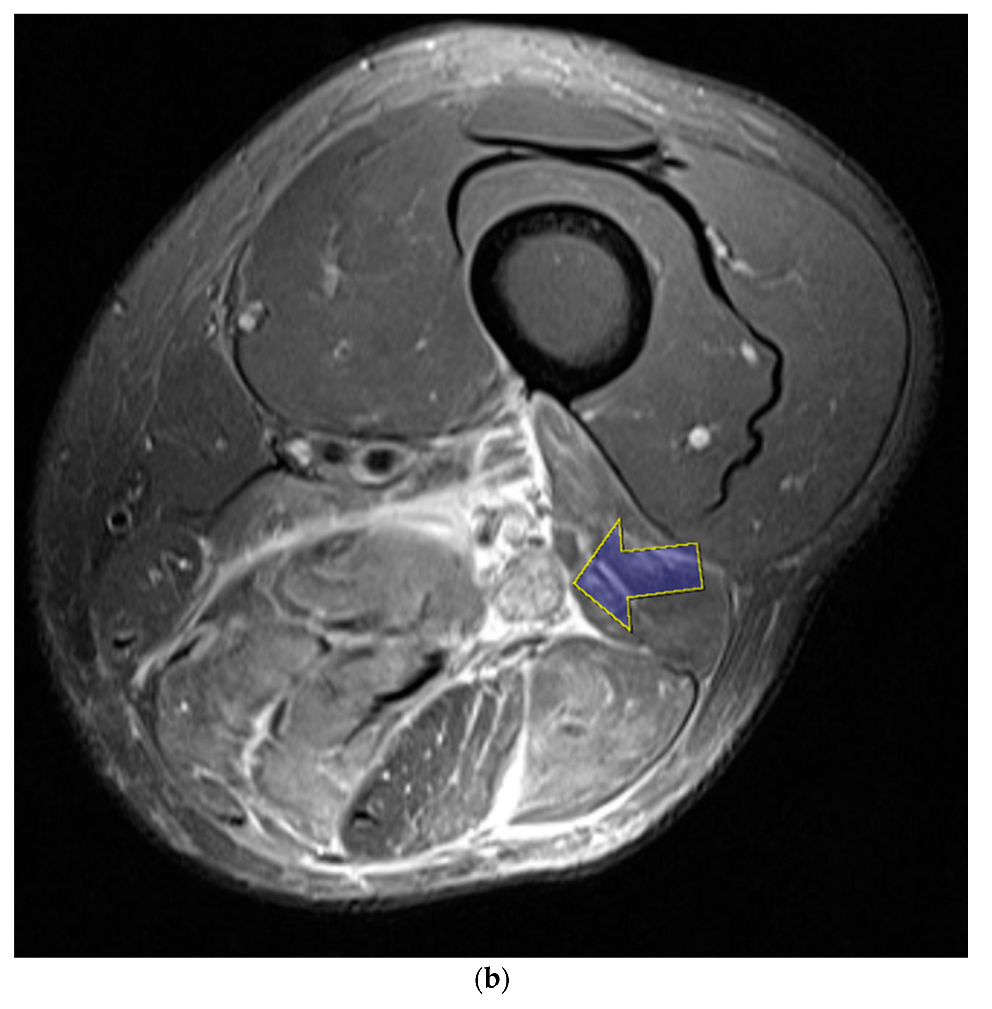

Nerve conduction velocity/electromyography (EMG) was performed and showed a severe sciatic nerve injury at the distal thigh level. Moreover, on computed tomography (CT), ischemic changes were observed in the adductor magnus, biceps femoris long and short head, semimembranosus, and semitendinosus muscles 25 cm below the femoral head, and the length of the lesion was approximately 6 cm (Figure 2a,b). The sciatic nerve in the affected area was observed to be swollen compared to the contralateral side, and the intermuscular fat was accompanied by haziness. Ischemic changes were observed in the posterior thigh muscles on magnetic resonance imaging (MRI), similar to the previous CT scan. In addition, the sciatic nerve was severely swollen compared with the contralateral side, and the T2-weighted signal intensity was increased (Figure 3).

Figure 2. Computed tomography (CT) scan with contrast reveals ischemic changes in the adductor magnus, biceps femoris long and short head, semimembranosus, and semitendinosus muscles from 25 cm below the femoral head (blue arrow) in coronal view(a) and axial view(b).